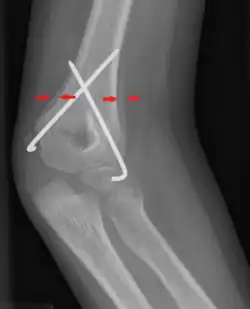

Periosteal reaction on a healing supracondylar fracture

A periosteal reaction is the formation of new bone in response to injury or other stimuli of the periosteum surrounding the bone.[1] It is most often identified on X-ray films of the bones.

The morphological appearance can be helpful in determining the cause of a periosteal reaction (for example, if other features of periostitis are present), but is usually not enough to be definitive. Diagnosis can be helped by establishing if bone formation is localized to a specific point or generalized to a broad area. The appearance of the adjacent bone will give clues as to which of these is the most likely cause.

Appearances include solid, laminated, spiculated, and the Codman triangle.[4]